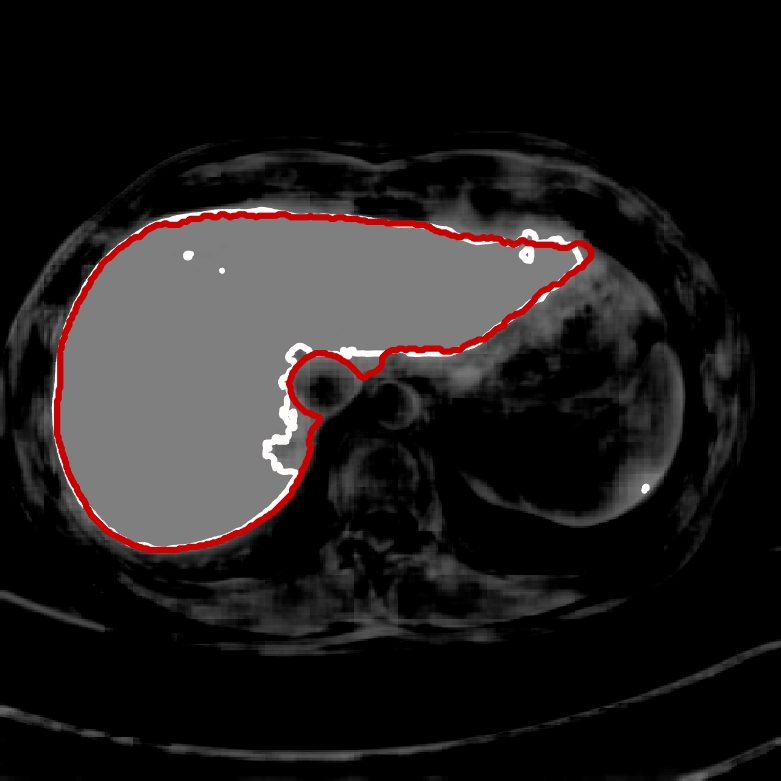

Figure 1 shows the results of the four individual segmenters. The grey level intensity reflects the probability map of foreground versus background. The white contour is the proposed segmentation boundary obtained by thresholding the probability map at 0.5. The red contour is the ground truth. 999The image for this example is slide 11 from the data of patient number 4 in the CHAOS dataset.

| U-net | Deepmedic |

|

|

| V-net | Dense V-networks |

|

|

In order to show the advantage of the ensemble, we chose a small, notoriously difficult, region to zoom on: vena cava superior (the blue rectangle in the U-Net plot in Figure 1). Figure 2 contains five plots of the segmented region. The product combiner was chosen for the ensemble. The ground truth is shaded in blue in the ensemble plot, and in red in the plots for the individual segmenters. The guessed segmentation is overlaid in transparent grey. The Dice score for the chosen area is shown under each plot. A Dice score of 1 indicates perfect segmentation while lower values indicate mismatch. As the results show, both visually and through the numbers, the ensemble segmentation is better than any of the individual ones.